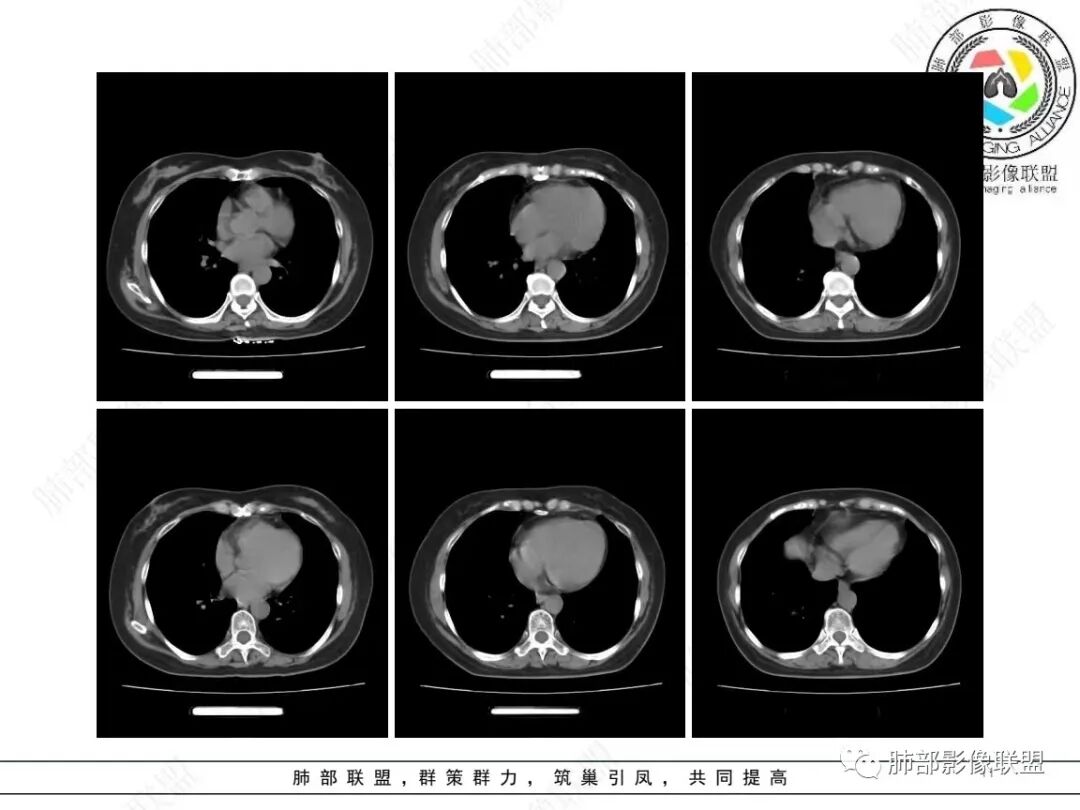

右下肺团片影,有胸膜牵拉,但是收缩力不强,有支气管充气征,有空洞,周围有晕。考虑炎性肉芽肿,鉴别腺癌。

右肺下叶团块影,边缘收缩为主,边界模糊,其内可见空气支气管征,边缘可见胸膜牵拉,明显强化,考虑炎性肉芽肿病变,鉴别腺癌。

中年女性,体检发现,右肺下叶基底段不规则肿块影,有胸膜牵拉,有细小毛刺,周围有晕,似有分叶及空泡?支气管进入后截断,明显强化?考虑肉芽肿性炎,鉴别腺癌。

右肺下叶结节,边缘有分叶毛刺,病灶内可见支气管扩张,胸膜牵拉,强化明显,所有征象都倾向腺癌,但是冠状位矢状位及纵膈窗显示病灶有点散散的感觉,周围还有长条索,考虑慢性炎症,鉴别腺癌

右肺下叶实性病灶,形态不规则,有分叶、毛刺,边缘见边界清晰磨玻璃影,病灶内可见扭曲扩张的细支气管,胸膜牵拉凹陷,考虑恶性病灶,腺癌可能,鉴别机化性肺炎,建议增强扫描及CT下穿刺活检。

病灶的收缩力不强,如果是肿瘤,那最可能是低分化腺癌,但是里面又有穿行支气管,又不符合低分化癌表现,所以腺癌的依据不是很符合,先考虑一个慢性机化性炎症可能大,但是不能完全排除腺癌的可能

右肺下叶不规则团片影,边缘模糊,收缩,长索条,其内支气管充气扩张,结构松散,延迟强化,考虑炎性肉芽肿,腺癌待排

中年女性,右肺下叶不规则团片影,边缘不清,感觉较散,内见支气管通过,增强明显强化。

考虑慢性炎症并机化性肺炎。鉴别腺癌